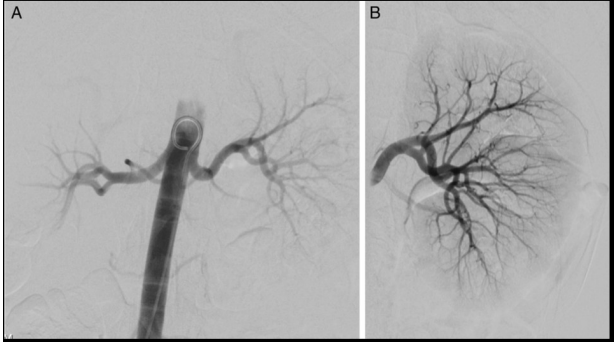

M.P.V., do sexo feminino, de 20 anos, foi encaminhada ao ambulatório de nefrologia para avaliação de hipertensão resistente diagnosticada aos 16 anos, com várias medidas de pressão arterial maiores que 150/90, em tratamento com amlodipino 10 mg/dia, valsartana 320 mg/dia e hidroclorotiazida 25 mg/dia. A paciente também relatava síndrome do ovário policístico e estava tomando anticoncepcional oral (etinilestradiol/drospirenona). Ela se absteve de álcool, drogas ilícitas, tabaco e medicamentos de venda livre. Ambos os pais tinham hipertensão diagnosticada na faixa dos 30 anos e nenhum deles apresentava uma causa secundária conhecida de hipertensão. Ao exame físico, achados normais, exceto pela pressão arterial; índice de massa corporal de 20,4 kg/m², sem alterações retinianas, hirsutismo, estrias ou edema periférico. Os exames laboratoriais revelaram atividade de renina plasmática (PRA) > 181,7 ng/mL/h e concentração plasmática de aldosterona de 215 ng/dL, repetida e confirmada. A paciente fez uma arteriografia (imagens abaixo), o anticoncepcional foi suspenso definitivamente e um tratamento específico foi instituído, com bom controle dos níveis pressóricos.